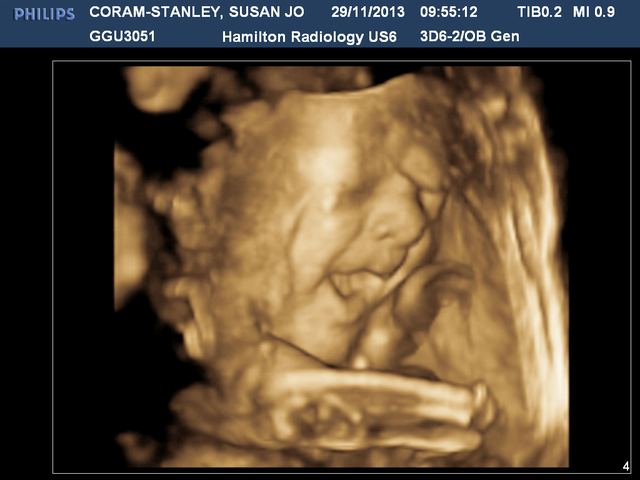

At 32 weeks we got a 3D scan. We combined this with our dating scan so were in there for AGES. But the scan was amazing, was so incredible seeing baby move about in there, in 3D. He waved and waggled his fingers, did a huge laugh - or cry or something, and just seeing him was truly incredible.